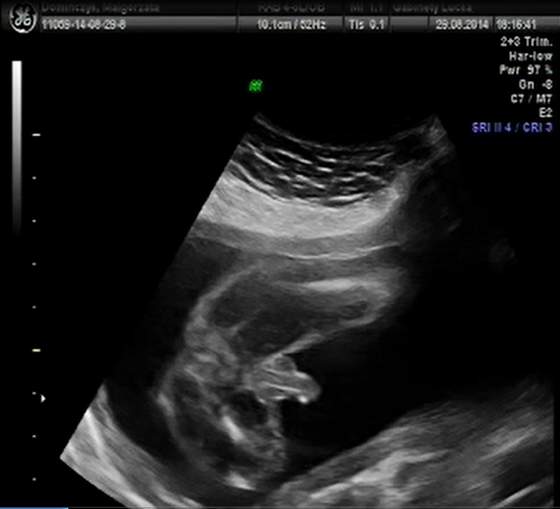

Na naszym piątkowym usg mój szkrab chętnie pokazywał tylko jedną część ciała:

Z resztą było dużo gorzej bo strasznie się wiercił tak, że nawet pani dr która robiła badanie stwierdziła, że wyjątkowo ruchliwy jest i nawet chwili nie usiedzi w jednym miejscu. I dostał ksywkę "sprinter"

Ale męczyliśmy go dość długo (badanie trwało 50min) i sprawdzone zostały wszystkie niezbędne parametry. Z czego wynika, że waga obywatela to już ponad 500 gram.